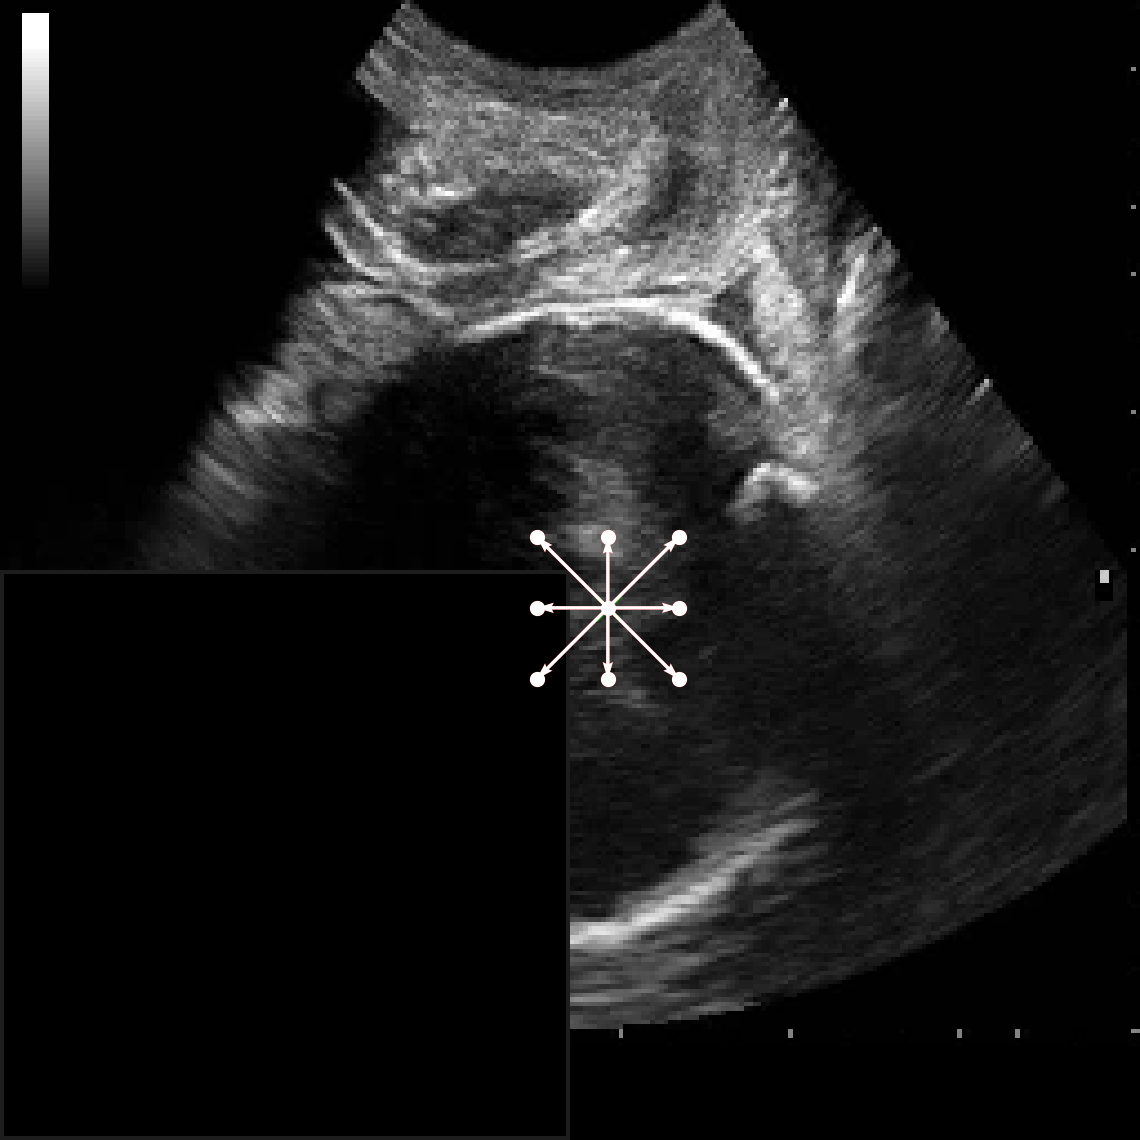

In practical clinical settings, medical images are often incomplete or degraded due to occlusions, artifacts, or limited fields-of-view. Therefore, a reliable segmentation model must be robust to missing spatial context and capable of inferring anatomical structures from partially observed inputs. To evaluate this critical property, we conducted a masking experiment using the FH-PS-AoP dataset. In this experiment, we systematically removed one quadrant from the input image, top-left, top-right, bottom-left, or bottom-right, and evaluated the performance of DAUNet compared to the baseline UNet.

Figure 7 presents a comprehensive visual comparison of the predicted offset maps and segmentation masks under each masking condition. The first column shows the original (unmasked) input along with its corresponding predictions, while subsequent columns depict the results for each of the masked quadrants.

DAUNet demonstrates markedly higher resilience to missing context compared to UNet. Its predicted offset maps remain dense and structured, with vectors that preserve anatomical directionality even when significant regions of the input are absent. This behavior reflects DAUNet’s ability to infer context from the remaining visual cues. In contrast, UNet exhibits sparse or disoriented offsets in the masked scenarios, indicating reduced spatial awareness and compromised localization.

To better understand this phenomenon, we analyzed the receptive fields of both models. For a representative pixel, we visualized its corresponding receptive area contributing to the output. In UNet, the receptive field is fixed and grid-constrained (refer to second row of Figure 7), making it sensitive to occlusions. On the other hand, DAUNet leverages deformable convolutions to dynamically adjust its receptive field based on the visible content. This adaptability is evident in the red and white arrows in the fourth column of Figure 7, where DAUNet modifies its offset patterns to account for the masked input.

The segmentation masks in third and fifth rows of Figure 7, further substantiate these findings. DAUNet consistently produces anatomically plausible segmentations of both the fetal head (green) and pubic symphysis (red), with minimal degradation even under 25% missing input. The output contours remain smooth, accurate, and well-aligned with ground truth boundaries. In contrast, UNet’s performance deteriorates noticeably, with fragmented or distorted segmentations, especially around the fetal head, as indicated by white arrows in the figure.

These results highlight the efficacy of DAUNet’s architectural innovations. The proposed combination of deformable convolution and SimAM attention allows the model to effectively reason over the visible context and compensate for spatial omissions. This robustness to incomplete inputs makes DAUNet well-suited for deployment in real-world medical environments, where noise, occlusions, and partial data are common challenges.